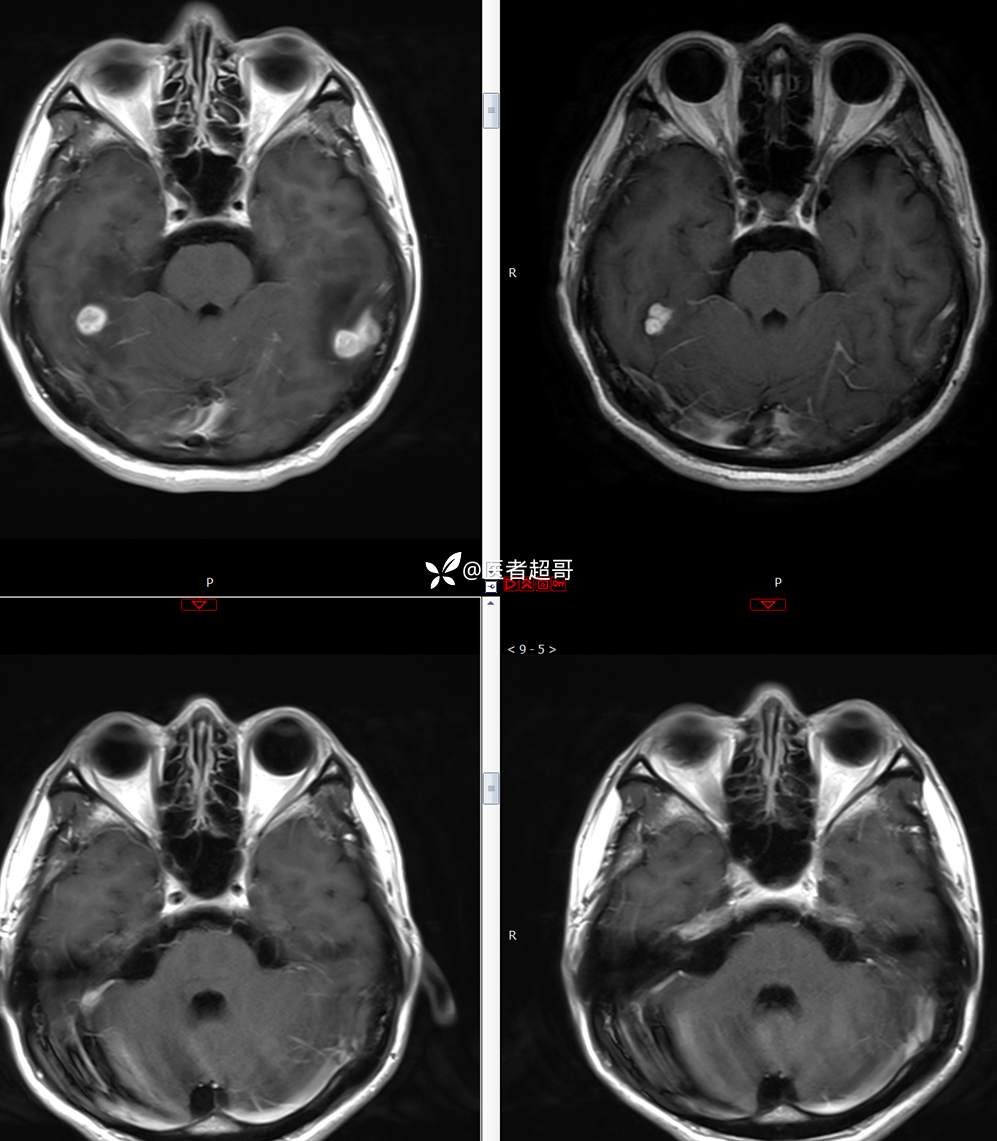

【影诊笔记773】头痛、头晕10天,CT、MRI齐全,请高诊!

主 诉:头痛、头晕10天

现病史:患者10天前无明显诱因感头痛、头晕,伴记忆力减退,无恶心、呕吐,无肢体抽搐及肢体活动不灵等,于我院就诊,行颅脑MR示颅内多发占位,现患者为求进一步治疗于我院就诊,以“颅内占位”收入我科。患者目前神志清,精神可,饮食、睡眠正常,体重无明显变化。

既往史:既往急性肝功能衰竭病史.